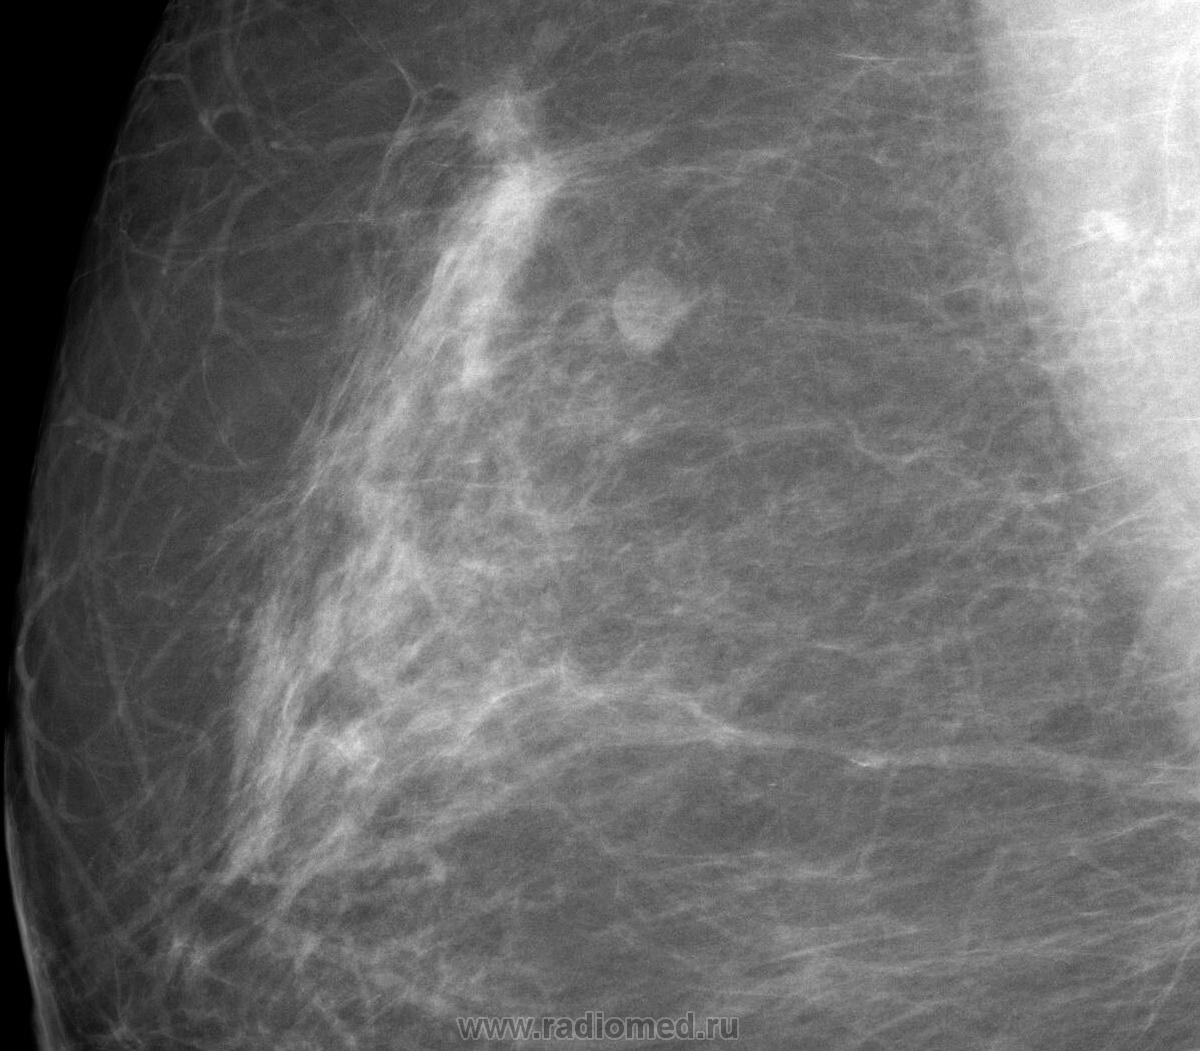

Случай 3.   Профилактическая маммография.  Рак молочной железы в виде "узлового образования".

"Узловое образование", состоящее из нескольких опухолевых узлов, неоднородной структуры, с неровными, нечеткими, полициклическими контурами. Пациентка направлена в онкологический диспансер, взята на учёт, прооперирована.